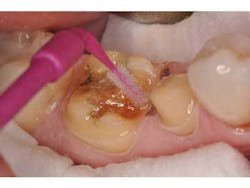

Before preparing the tooth surfaces for bonding, it was noted that the interproximal gingival col showed evidence of mild gingivitis (Fig. 4). This is not an infrequent problem, because patients may not maintain the same levels of hygiene around provisional restorations as they would around natural teeth. In this case, the splinted provisional crowns were unable to be flossed and likely contributed to the gingival irritation. A hemostatic paste (Traxodent, Premier) was applied to quell the bleeding (Fig. 5). This paste sets quickly and is able to maintain its position while further steps are taken.

The exposed dentin and enamel surfaces are first treated with a chlorhexidine antibacterial slurry (Conspesis Scrub, Ultradent) to remove residual provisional cement and lower bacterial loads (Fig. 6). This step has been shown to increase the bond strength of adhesive resin cements. (8) After wash and removal of the hemostatic and antibacterial solutions, the area was able to be isolated with dry cotton rolls. If isolation is difficult, the clinician may choose to place a rubber dam. The decontaminated and isolated tooth surfaces are treated with a self-etch primer (Multilink Primer A and B, Ivoclar) (Fig. 7). After drying and light-curing the teeth, the restorations are filled with a dual-cure adhesive resin cement (Multilink Automix, Ivoclar) and seated. Excess cement is removed and the final restorations may be polished (Fig. 8).